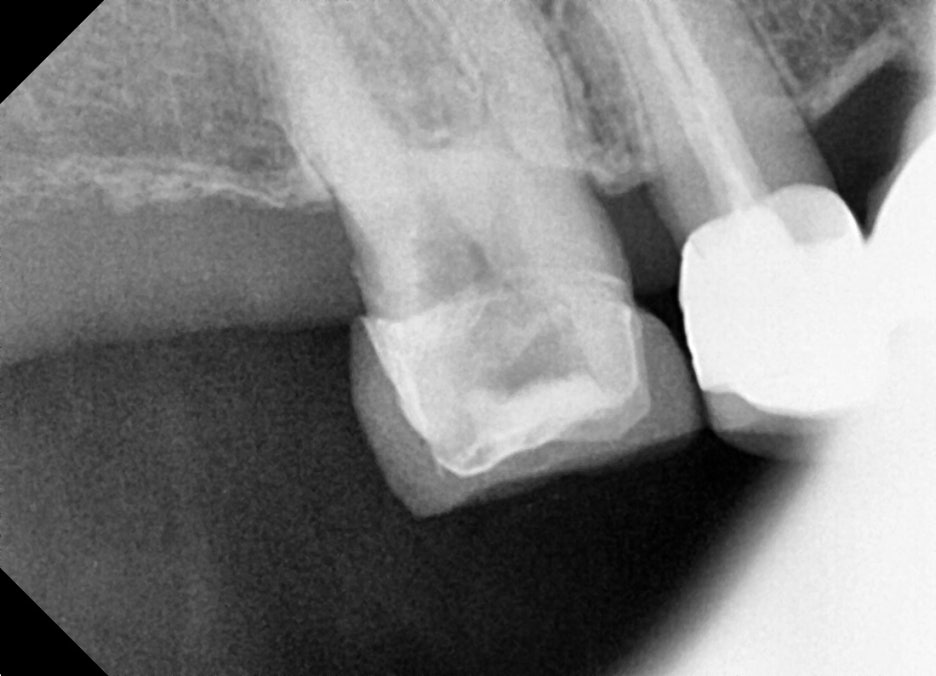

For a more precise assessment, an additional periapical X-ray was taken, and it was confirmed that the inflammation had spread all the way to the root tip of the tooth. At this stage, the root canal treatment plan was finalized.

Root canal treatment refers to drilling out the surface of the tooth, removing the inflammation inside, and then covering the tooth with a restoration.

Second root canal treatment

– Canal shaping and cleanup of infected tissue

During the second treatment, which the patient returned for one week later, the process of removing the fine inflammatory tissue remaining inside the canal was carried out.

Once the shape of the canal has been stably organized, the next step can proceed to final filling (root canal obturation).